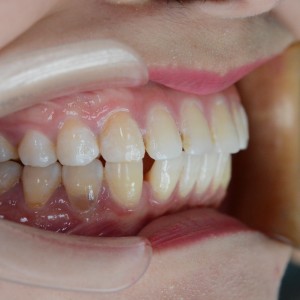

術(shù)后

更新時(shí)間:2021-07-29 16:54:58 項(xiàng)目:#牙齒矯正 所屬醫(yī)院:廈門拜博口腔醫(yī)院 所屬醫(yī)生:張忠

總是對自己的牙齒都很不滿意,別人的牙齒不好可能是牙外突或內(nèi)凹,但我的牙齒是牙縫太大,感覺牙齒很松,說話漏風(fēng)。于是便一直想把牙齒整整齊齊,但想到要等很久才能再提起熱情。

并沒有很想用傳統(tǒng)的牙齒矯正方法,感覺看起來不好看呀,之前猶豫其實(shí)也有這個因素。但是最近終于下定決心矯正牙齒,選擇矯正牙套,這樣看起來不會那么明顯,而且摘戴也更方便。